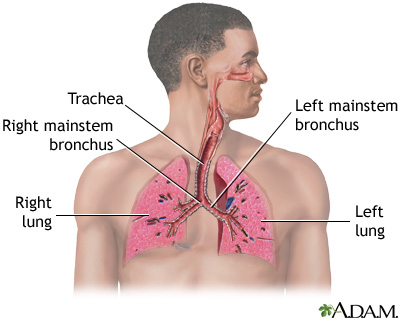

A collapsed lung occurs when air escapes from the lung. The air then can fill the space outside of the lung between the lung and chest wall. This buildup of air puts pressure on the lung, so it cannot expand as much as it normally does when you take a breath.

The medical name of this condition is pneumothorax.